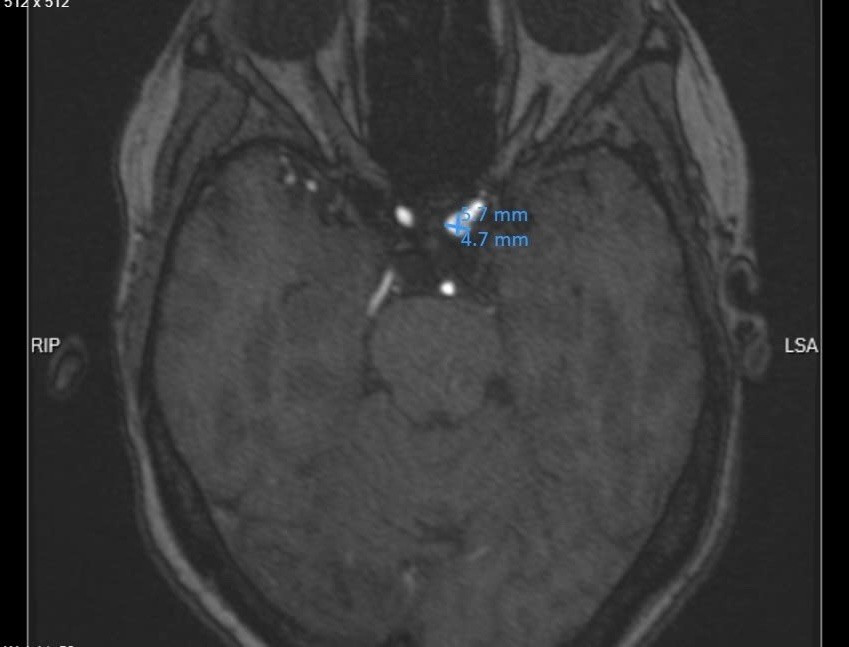

Qua thăm khám lâm sàng, các bác sĩ đã chỉ định chụp cộng hưởng từ mạch máu não. Kết quả ghi nhận bệnh nhân có túi phình mạch tại đoạn siphon của động mạch cảnh trong trái, kích thước khoảng 5 - 6 mm, thuộc nhóm túi phình mạch não kích thước trung bình.

Túi phình mạch máu não trên phim chụp - Ảnh BVCC